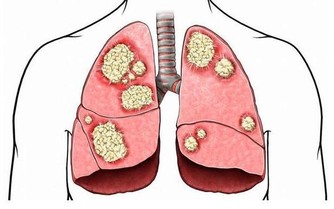

肝癌是一種多發的惡性腫瘤疾病,根據數據統計,我國每年都會有14萬左右的新增肝癌患者,其中有11萬左右的人因為肝癌死亡,這個數據佔全球肝癌死亡人數的45%。嚴重地威脅著人們的生命。

大多數肝癌患者在早期都不會有明顯的不適症狀,且大約有80%的人發現疾病之後都已經進入中、晚期,加上人們對癌症的恐懼感更是使治療難度增大。如果是早期發現肝臟,通過積極地治療也有著70%的治愈率,所以人們要培養起對肝癌早期篩查以及預防的意識。當身體出現以下兩紅、兩痛的症狀後,建議大家到醫院做個肝臟檢查。